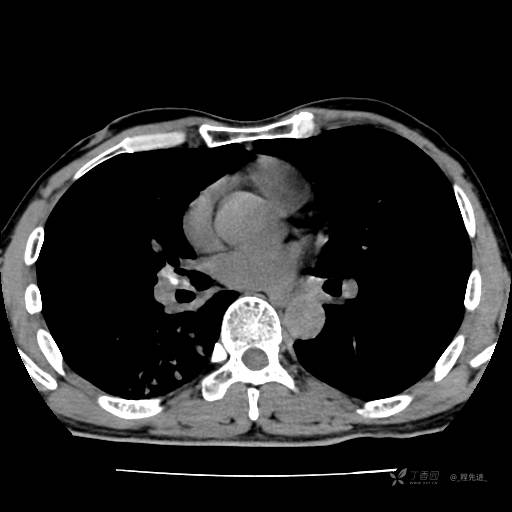

2月特别精彩病例|咳嗽、咳痰20余天,典型病例分享【结果已公布】

患者年龄:51岁

主诉:咳嗽、咳痰20余天

简要病史:20余天前开始出现咳嗽、咳痰症状,阵发性刺激性咳,白色粘痰,不易咳出,无发热,无咯血,无恶心、呕吐等不适,未诊治,咳嗽、咳痰症状持续存在。

体格检查:T:36.3 ℃ P:79 次/分 R:20 次/分 BP:128/64 mmHg,神志清楚,呼吸平稳,双肺呼吸音粗,右下肺闻及细湿性啰音。心率79次/分,节律整齐,各瓣膜听诊区未闻及病理性杂音。腹部未见异常,双下肢无水肿。

辅助检查:我院门诊胸部CT示:如下。心电图:窦性心律;正常心电图。